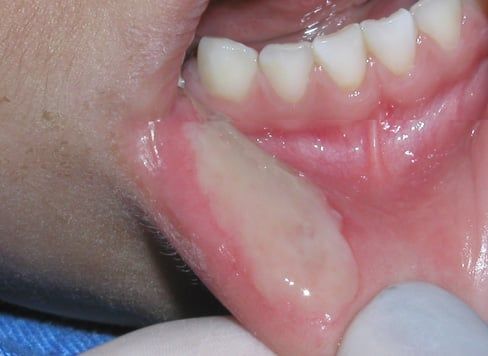

Mucocele

This is a common benign lesion in children and adolescents that results from the rupture of the excretory ducts (very small tubes) that deliver saliva to the top tissues of the lips. More than 75% of mucocele are located on the lower lip and their size and color may vary, however, they tend to be relatively painless for the most part. Most of the time, patients report that these "bumps" grow until they burst spontaneously, leaving small ulcers that heal within a few days. This does not mean the lesion is gone, as they often tend to re-appear weeks or months later. Most dentists will recommend surgical treatment for these lesions.